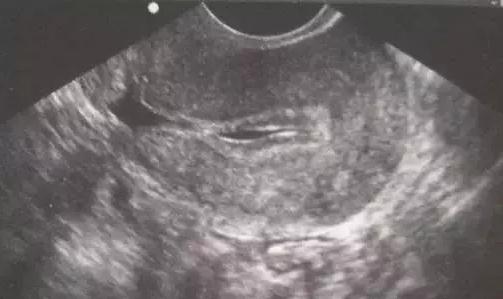

如上图所示,在B超检查过程中发现宫腔内有液性暗区,就称为宫腔积液。助孕治疗过程中宫腔积液出现的几率为2.95%~8.2%。

(3)剖宫产切口愈合不良和宫腔粘连:如第一幅图片绿色箭头所示,这是剖宫产术后导致的子宫憩室,液体淤积不能排除导致反复出现宫腔积液;各种原因引起的宫腔粘连使宫腔内液体不能顺利流出导致宫腔积液。